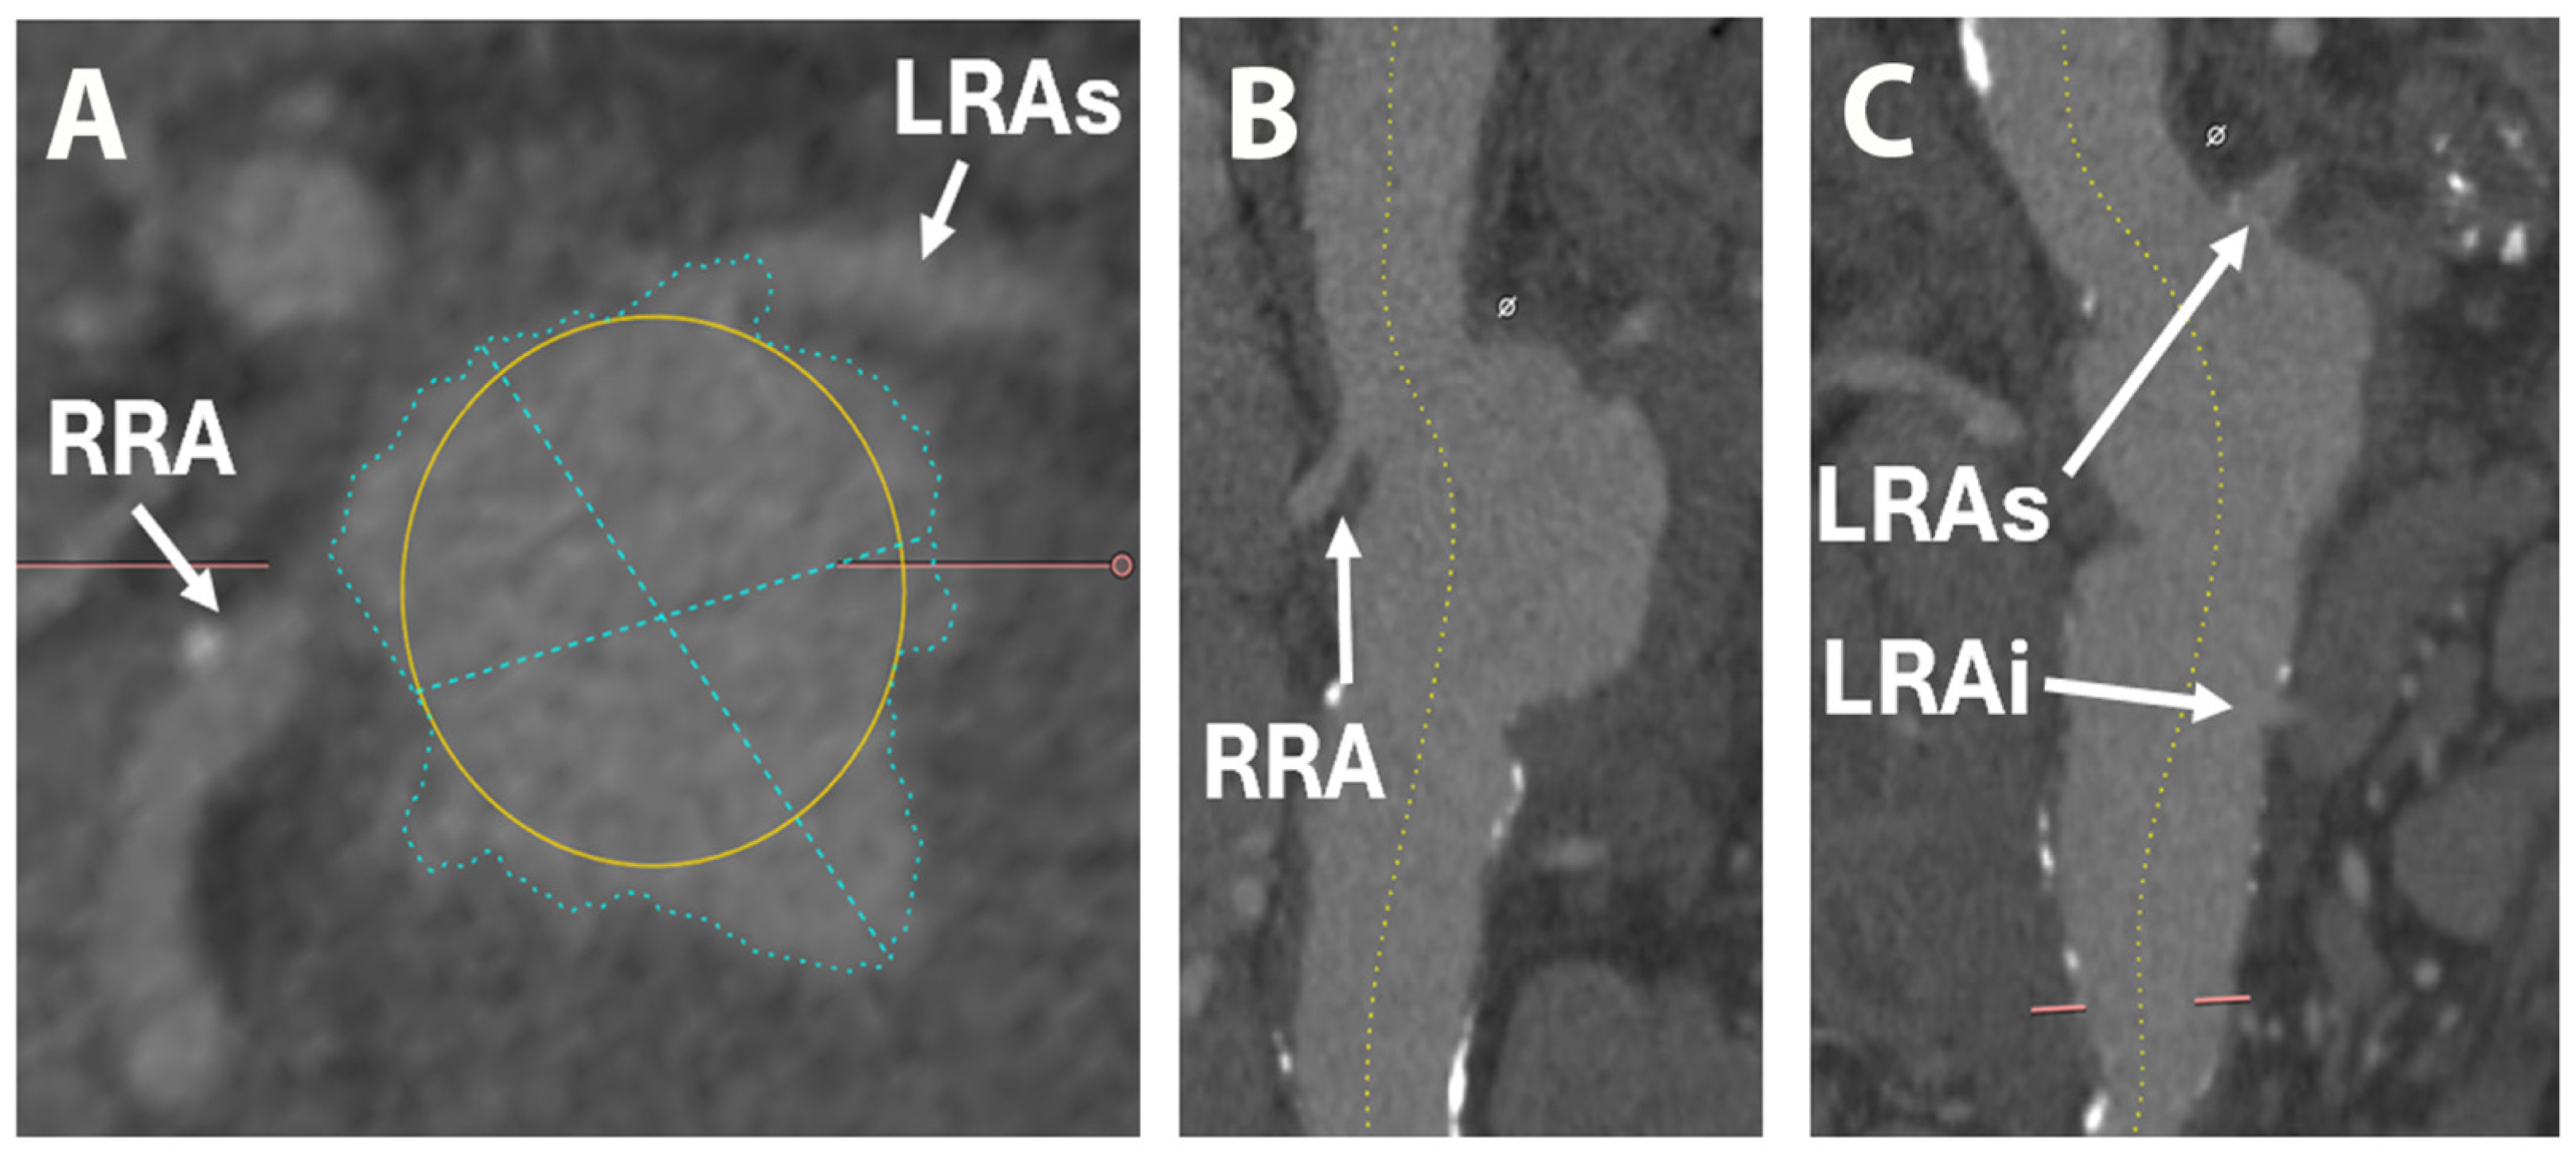

2. Case Report